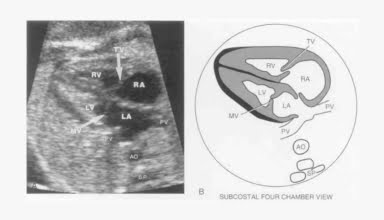

[Video] Siêu âm tim thai, TS Lê Kim Tuyến

Siêu âm tim thai là bài giảng trong Khóa học Siêu âm Sản phụ khoa (BV Từ Dũ) do TS Lê Kim Tuyến giảng dạy.